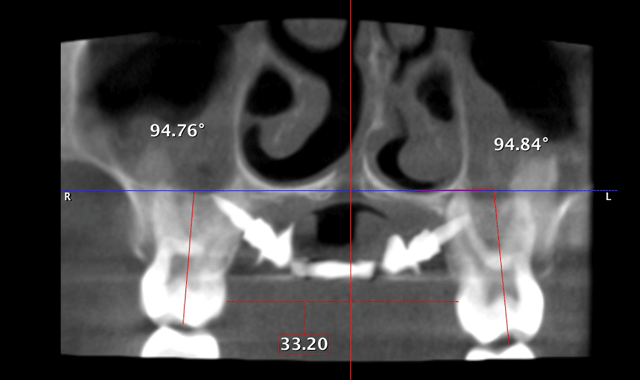

We can now extrapolate a coronal view that allows us to visualize many anatomical structures to formulate a diagnoses and treatment plan. The coronal view with a slice taken through the lingual roots of the maxillary first molars can be used to accurately determine the width of the maxilla and the inclinations of the maxillary molars (Fig. 5). We can then determine the mechanics needed for our patients in this dimension. The mechanics utilized on the patient in Figure 5 were expanded with skeletal fixation of the expander. No bands were attached to the molars.

Therefore, true horizontal expansion was achieved (Figs. 6a, 6b, 6c). These images were taken at the ULD settings on a Planmeca ProMax 3D Mid. Before placing stainless steel wires, many orthodontists will take a progress pan. to evaluate the roots of the teeth as far as proper bracket placements. This is an additional 35 microsieverts when using a traditional 2D panoramic machine. The ULD setting on the Planmeca Pro-Max 3D Mid machine with a limited field of view that only images the teeth is an effective dose of around 9 microsieverts.